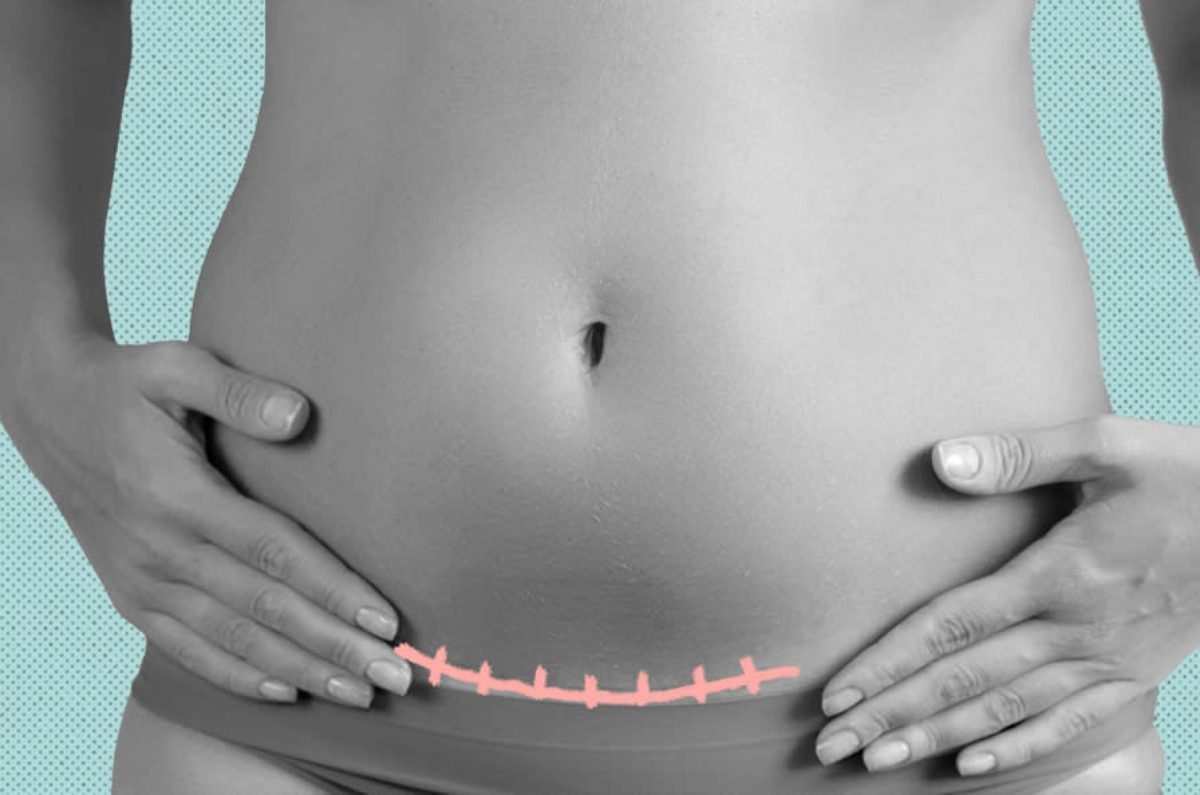

Sezaryen Dogum Sonrasi Hamilelik Dr Tugrul Abacioglu

Iki Dogum Arasindaki Sure Ne Kadar Olmalidir Op Dr Serkan Oral

Sezaryen Dogum Sonrasi Hamilelik Dr Tugrul Abacioglu